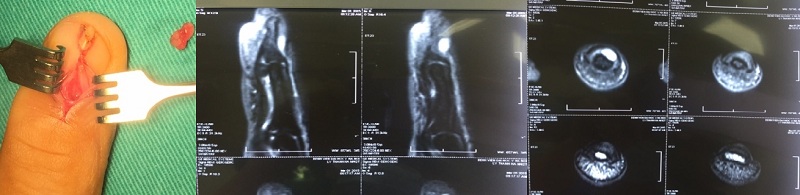

- Bệnh nhân thứ nhất: U cuộn mạch dưới móng

Siêu âm: có thể thấy một khối giảm âm dưới móng, tuy nhiên khó khăn trong 1 số trường hợp như khối u quá nhỏ hoặc nhiễu do móng tay bệnh nhân.

Cộng hưởng từ(MRI): có ưu điểm là trong trường hợp phát hiện ra thì sẽ đánh giá được chính xác khối u.

Điều trị: phẫu thuật là lựa chọn duy nhất khi đã có chẩn đoán xác định u cuộn mạch dưới móng. Kỹ thuật phẫu thuật tương đối đơn giản, hiệu quả phẫu thuật cao là những ưu thế được nhiều tác giả công nhận. Một hạn chế có thể là yếu tố thẩm mỹ trong trường hợp phải cắt bỏ 1 phần móng của bệnh nhân.